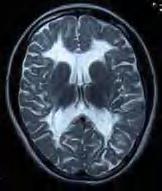

twarzy i obwodowych części kończyn. W postaci klasycznej, oprócz opóźnienia ruchowego i ataksji, w różnym okresie – po miesiącach, a nawet latach – dochodzi do rozwoju spastyczności. Obserwuje się ponadto elementy zespołu pozapiramidowego – u młodszych dzieci ruchy mimowolne, u starszych – dystonię. Rozwój umysłowy jest różny – od prawidłowego do niepełnosprawności intelektualnej w stopniu głębokim. Na ogół wzrok jest długo zachowany, mimo cech zaniku nerwów wzrokowych w badaniu dna oka. RM mózgowia ujawnia rozległą hipomielinizację istoty białej mózgu (z zajęciem torebek wewnętrznych, zwłaszcza odnóg tylnych), pnia mózgu i móżdżku – zmiany hiperintensywne w sekwencjach T2-zależnych (ryc. 5.1). U matek nosicielek istota biała może być niehomogennie zmieniona, z nieostrą granicą między korą a istotą białą.

Rycina 5.1. Choroba Pelizaeusa Merzbachera u 2-letniego chłopca. Niezmielinizowana, lekko hiperintensywna cała istota biała łącznie z torebkami wewnętrznymi. RM sekwencja T2-zależna.